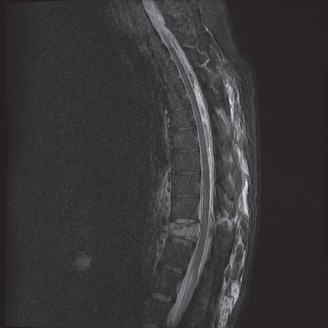

CASE 1 A 63-year-old male sustained a hyperextension injury to his neck while diving into a pool. Upon presentation, he reports decreased sensation in his hands and decreased strength in his arms and wrists, but no lower extremity complaints. On motor examination, he has 5/5 strength in his deltoids and elbow flexors and 4/5 strength in the elbow extensors, wrist extensors, and finger flexors. Lower extremity motor examination is normal. Sensation is decreased to light touch in both hands. Otherwise his sensation is preserved. Images of his cervical spine are shown in Figures 1–1 to 1–3.

The correct answer is (B). The clinical scenario describes a patient with central cord syndrome (CCS). CCS continues to be the most common incomplete spinal cord injury accounting for 15.7% to 25% of all spinal cord injuries. The characteristic presentation is an extension moment injury in a previously spondylotic and stenotic spine. Figures 1–1 to 1–3 demonstrate a spondylotic spine with central narrowing and CSF effacement that is worst at the C3–4 level. Bleeding, edema, and/or Wallerian degeneration lead to damage of the lateral corticospinal tract which is the main descending motor tract in the spinal cord. The more central anatomic position of the homunculus to the upper extremities places them at greater risk than those to the lower extremities. As such, injury to the lateral corticospinal tract is characterized by upper more than lower extremity involvement and motor deficits being more pronounced than sensory deficits.